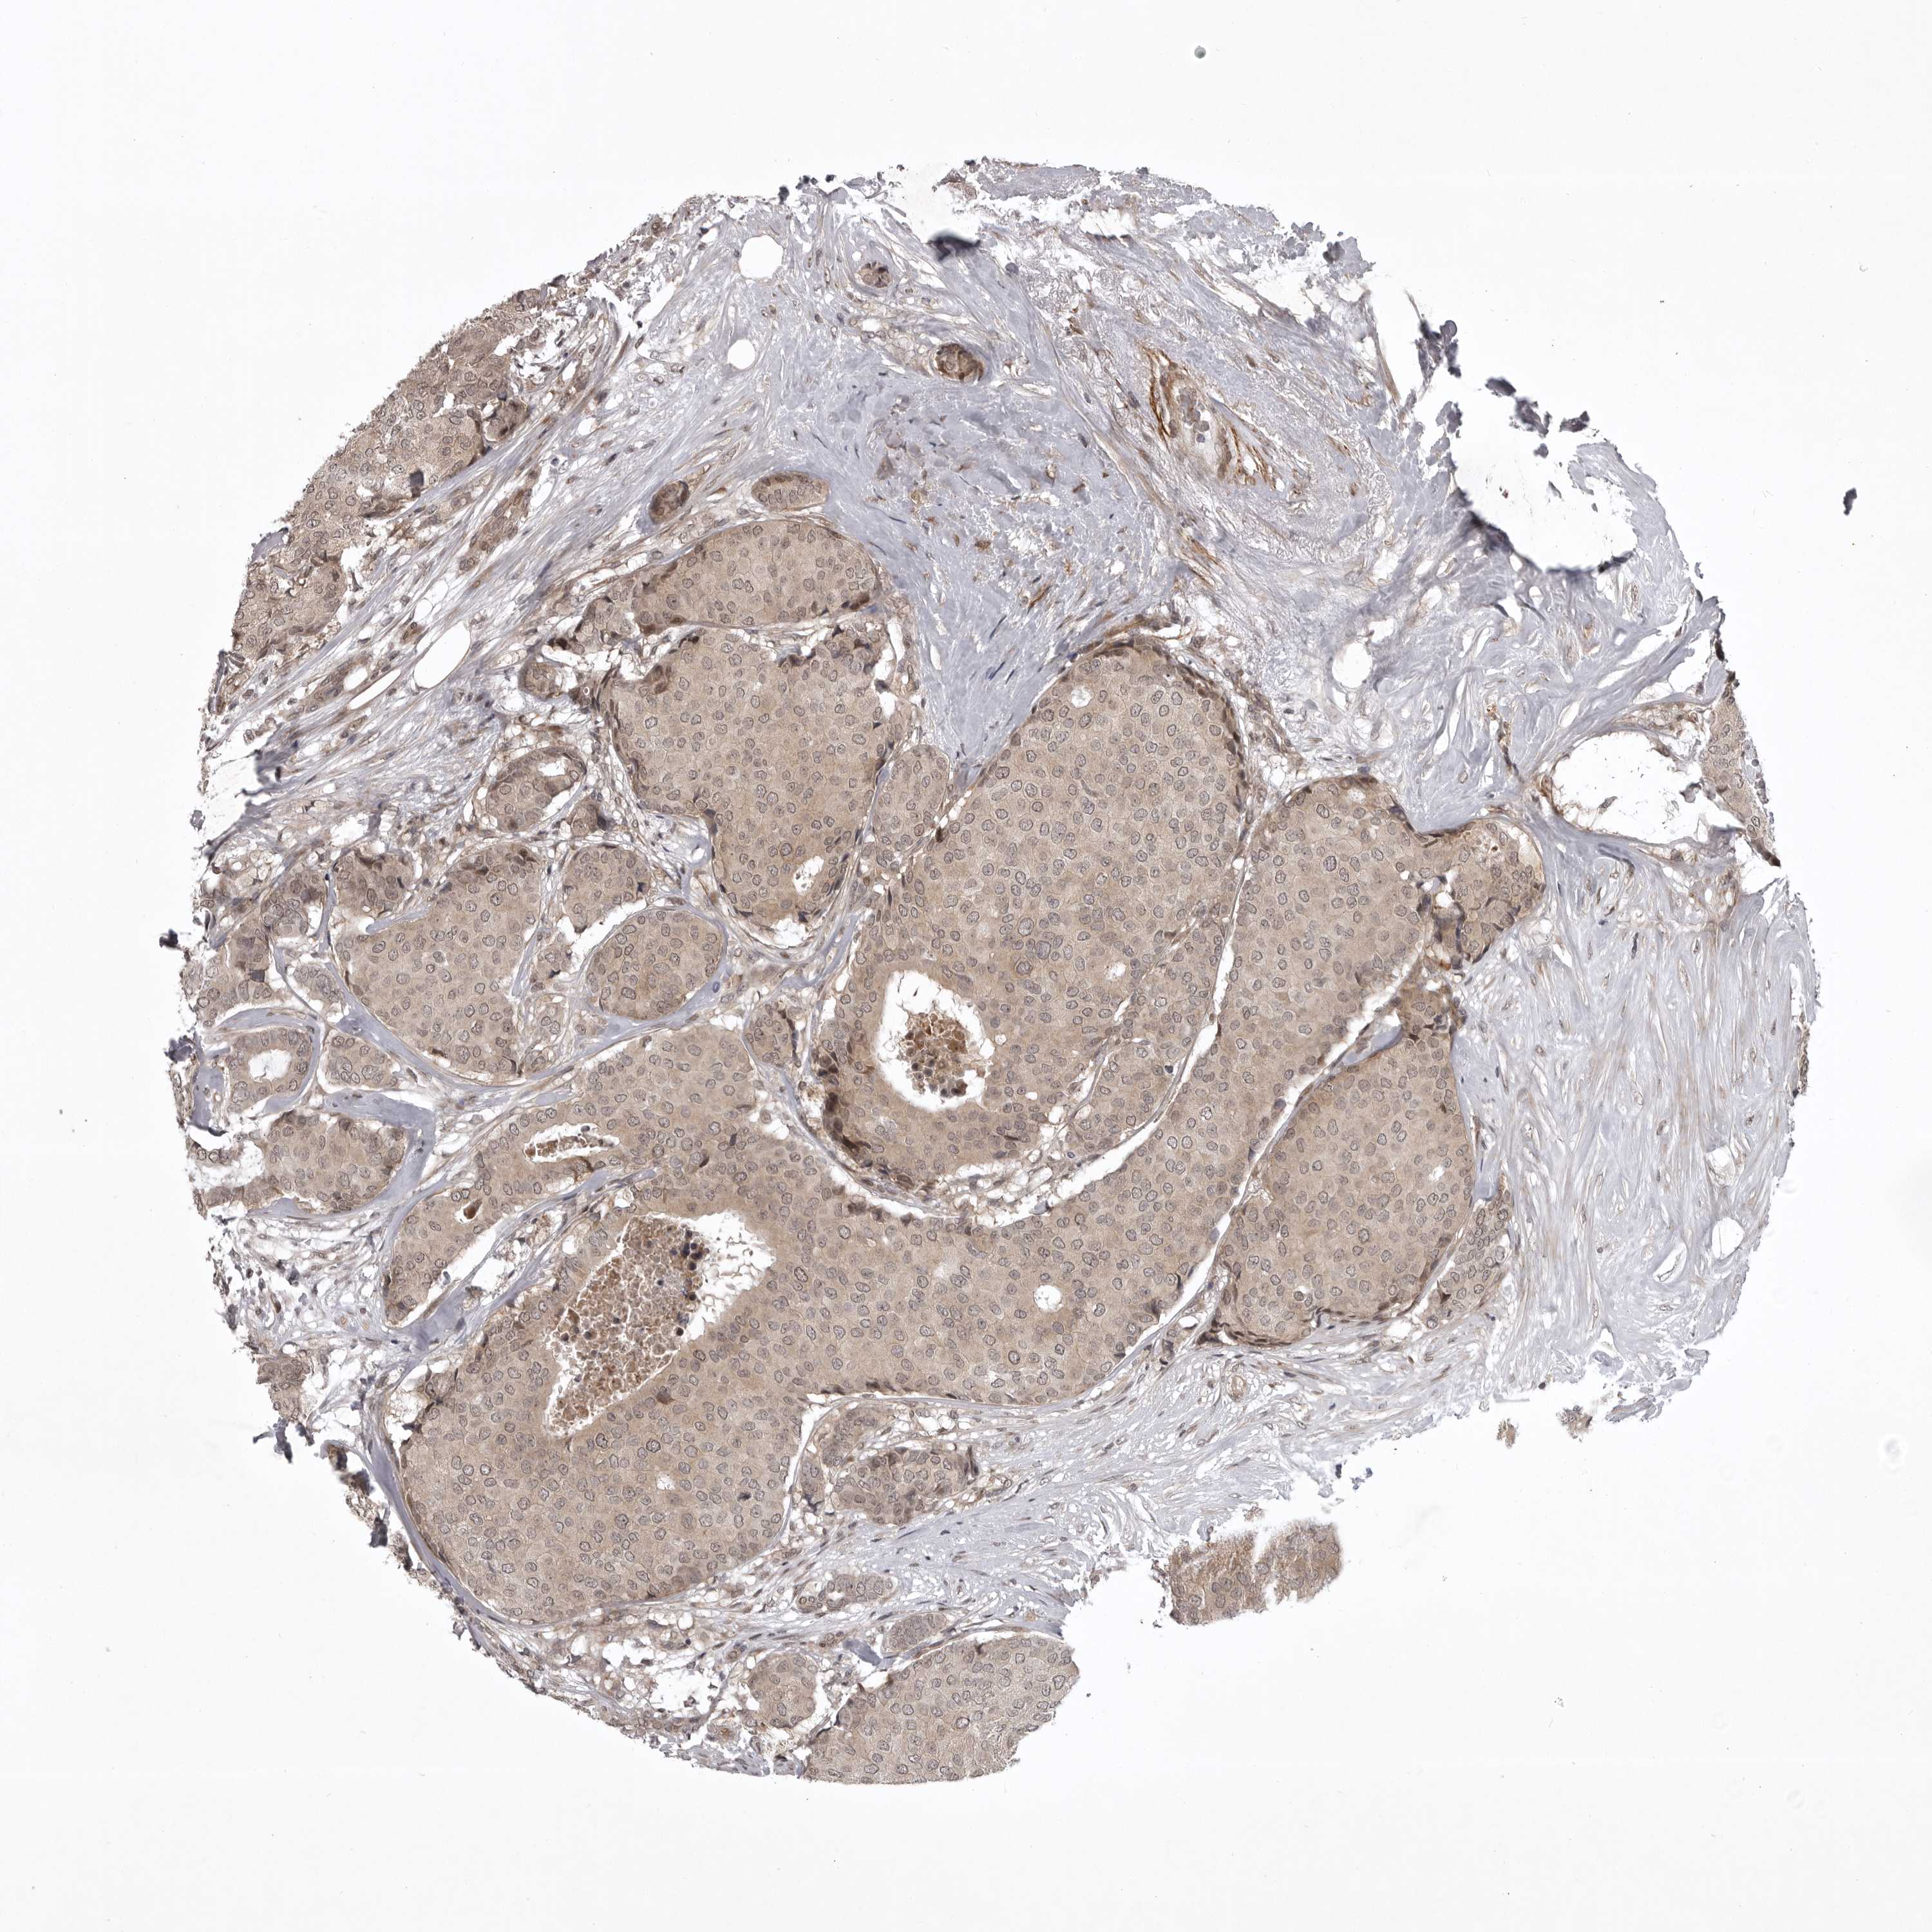

BRCA TCGA BRCA VALIDATION PROTEIN EXPRESSION

ANTIBODIES

AND

VALIDATION